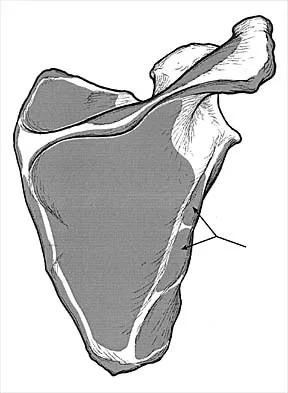

Which of the following nerves innervates the muscle that originates from the middle third of the dorsal surface of the lateral border of the scapula, as shown in Figure 7?